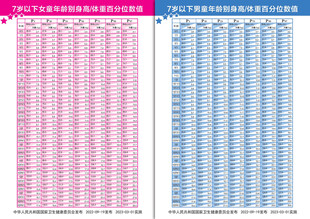

7岁以下男童女童年龄别身高体重 共享分:200

7岁以下男童女童年龄别身高体重 共享分:200 -